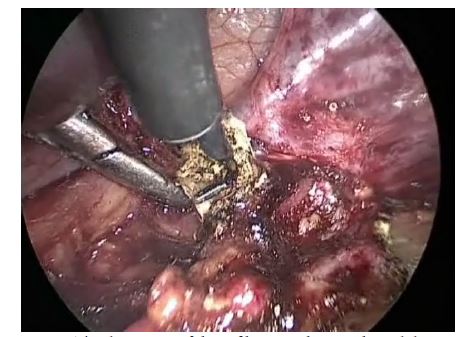

Cystoscopy was performed; the bladder was filled with 150 ml of physiological solution, the mucosa being without pathological changes. In the left ureter, the stent that had been placed before still functioned. The right ureter was located in the typical place, rhythmically excreting trickles of transparent urine. Within the proximal 0.5 cm of infiltrate, the main section of the ureter was intersected, the stent was removed. Endometrioid infiltrate was completely excised and evacuated from the abdominal cavity through the trocar hole. After excision of endometrioid heterotopy from the edge of the ureteral cut, the distal ureter was mobilized. The left ureter was stented again (Figure 6). Uretero-ureteral end-to-end anastomosis with 0000 Vicryl sutures was performed (Figures 7 and 8). No extravasation was observed in the anastomosis site.

| Figure 7: Fragment of the operation which demonstrates suturing the ureter |

| Figure 8: Uretero-ureteral end-to-end anastomosis with 0000 Vicryl sutures |